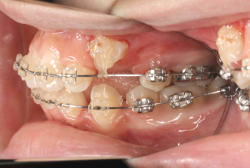

牽引(埋伏犬歯を牽引した症例)

埋伏歯とは、骨または歯茎の下に埋まって出てこない状態の歯のことを言います。埋伏歯があると歯が押されて歯並びが悪くなってしまったり、永久歯が生えてこれない原因になる恐れがあります。

「乳歯が生え替わらない」という主訴で来院したケースです。 診断の結果、「左上永久犬歯が第一小臼歯後方上部に埋伏しているため、左上乳犬歯が晩期残存している症例」と判明しました。

このような症状の場合は、手術で埋伏している永久歯に金具を取り付け、矯正装置で牽引する必要があります。同時に凸凹の解消と前突した前歯を内側に入れるために上下左右の小臼歯を抜歯させて頂くことといたしました。

この方の場合は、マルチブラケット装置にて治療を開始し、治療期間2年3ヶ月で終了しました。犬歯の牽引距離が非常に大きかったため当院の平均治療期間よりも大幅に期間がかかりましたが、埋伏犬歯を完全に正しい位置まで誘導することができました。同時に 前歯の前突と配列の凸凹も解消しました。

このような症例は、成人してしまうと埋伏歯の反応性が悪く、あまりにも動きが悪い場合は牽引をあきらめて抜歯する場合もあります。歯科医院の検診で親知らず以外の埋伏歯を指摘された場合は、できるだけ早く矯正専門医に御相談下さい。

マルチブラケット装置は、装置装着時より数日から2週間程度強い不快感疼痛が有りますが、本症例場合は埋伏歯を開窓手術し、遠く離れた位置に矯正器具が付いていますので強い違和感が生じ、歯ブラシも届きにくく口腔衛生状態を保つのにはかなりの努力が必要です。条件の悪い場所に接着されているため、装置が外れやすく日常生活上もかなり配慮が必要となります。

また、埋伏歯は移動距離が大きくなることが多く、歯根吸収のリスクが高まりますので、移動と休止にゆとりのある治療間隔が必要です。